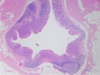

Normal Appendix

Appendicitis

Appendicitis

Appendicitis

Appendicitis